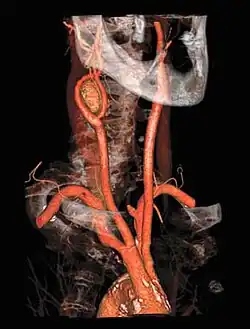

Angiography

CT angiography is a contrast CT taken at the location and corresponding phase of the blood vessels of interest, in order to detect vascular diseases. For example, an abdominal aortic angiography is taken in the arterial phase in the abdominal level, and is useful to detect for example aortic dissection.[10]